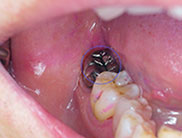

下の画像をご覧ください。

黒くなっている部分が処置すべき部分となります。

これらは肉眼だけではどうしても対応できません。目で確認できる限界があるためです。

しかし「マイクロスコープ」を利用すると、これらをしっかり目で確認した状態で治療を進められます。